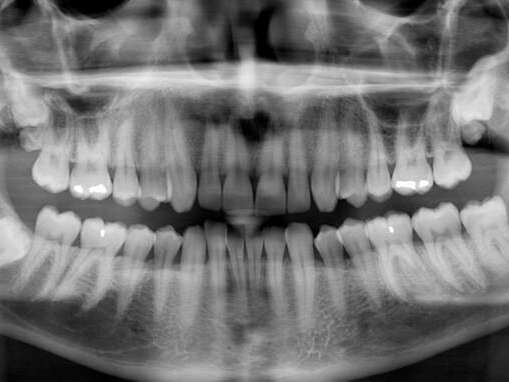

With our digital x-rays, we can get a more accurate and detailed picture of your teeth. We can see and discuss smaller issues before they become bigger and more costly problems. We believe in being conservative and helping you make an informed decision for your oral health.

Digital X-Rays and Sensors

Digital x-rays represent a leap in imaging technology, providing detailed views of your oral structure. This technology is pivotal in diagnosing conditions not visible during a regular dental exam, such as early tooth decay, gum disease, and infections. Digital x-rays are used across a spectrum of dental services and offer the benefit of lower radiation exposure, instant image processing, and enhanced diagnostic precision, ensuring you receive accurate and efficient care